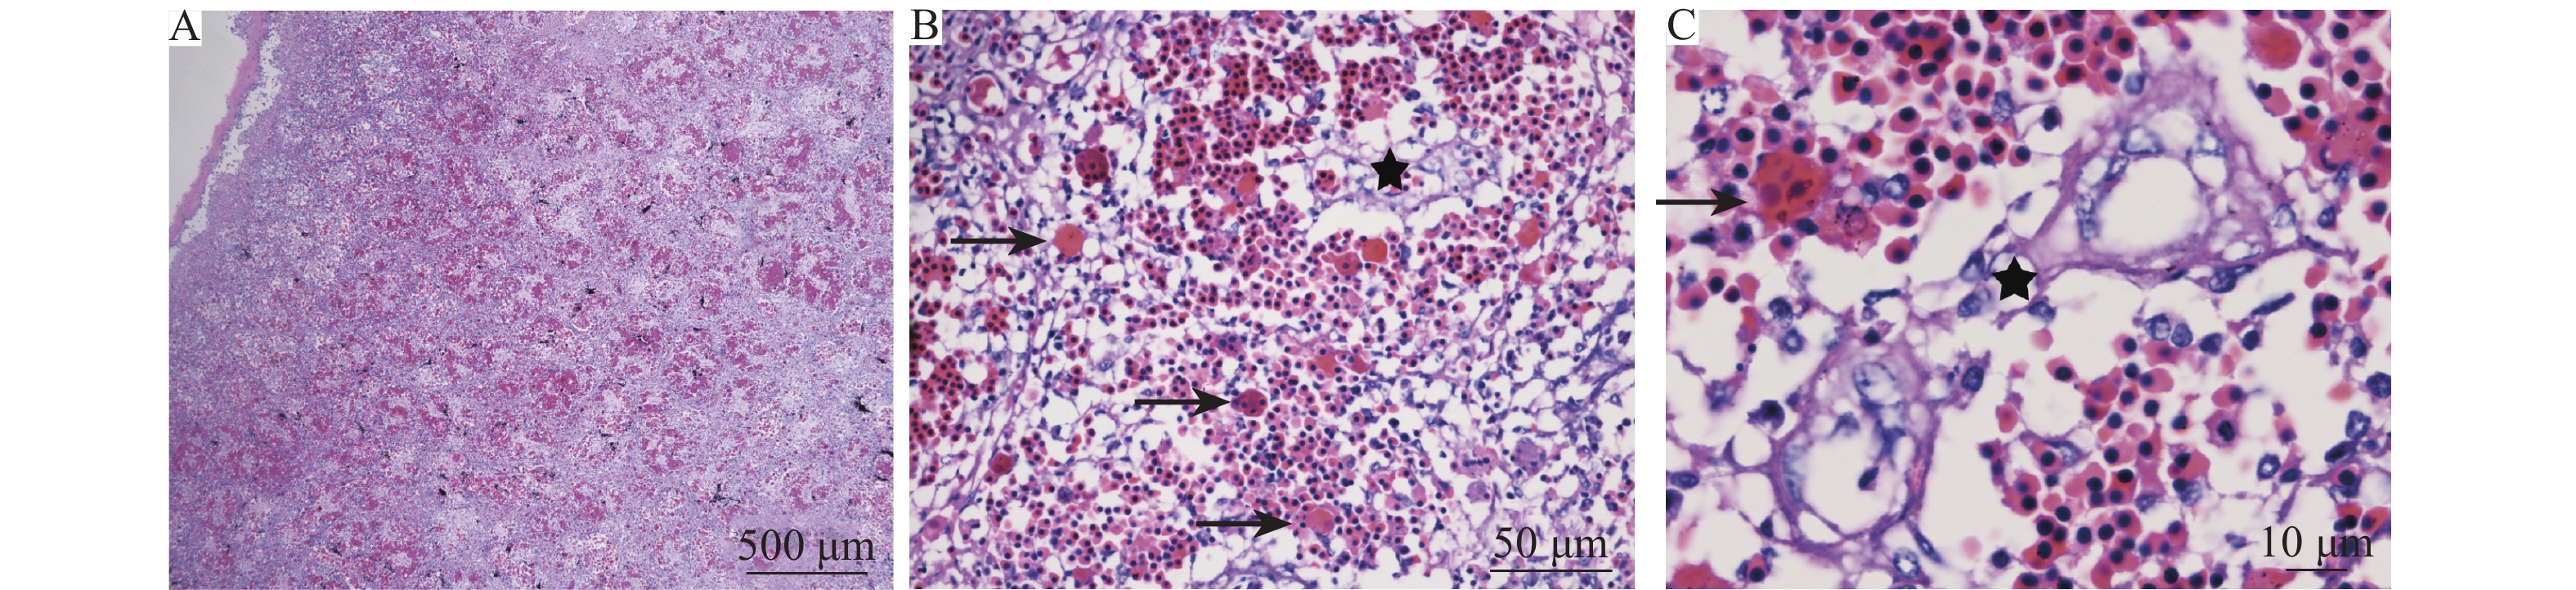

结果  该出血溃疡症的靶器官主要为脾脏、肾脏、肝胰脏、肠道以及皮肤肌肉。主要表现为严重的血管反应,实质细胞可见肿胀、变性、坏死;而胃、脑和心脏病变较轻,仅有轻微的炎症;鳃丝、眼球和鳔等未见明显病变。所有的患病个体均出现中度至重度出血性坏死性脾炎、中度肾炎、轻度至中度坏死性肝胰腺炎和肠炎。患病斑点叉尾鮰体内未检测到寄生虫、细菌以及CCV。

Result  The spleen, kidney, hepatopancreas, intestine, skin and muscle were the main target organs of hemorrhagic ulcer. The main syndrome was severe vascular response with degeneration and necrosis of the parenchymal cells. Stomach, brain and heart had minor damages with slight inflammation, and gill filaments, eyeballs and swim bladder did not have obvious pathological changes. The diseased individuals displayed moderate to severe hemorrhagic necrotic spleen inflammation, moderate nephritis, and mild to moderate necrotic hepatopancreatitis and necrotic enteritis. No parasite, bacteria, or CCV was detected in diseased catfish.